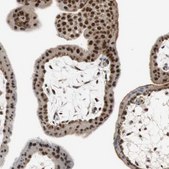

Anti-SIRT1 antibody produced in rabbit, a Prestige Antibody, is developed and validated by the Human Protein Atlas (HPA) project . Each antibody is tested by immunohistochemistry against hundreds of normal and disease tissues. These images can be viewed on the Human Protein Atlas (HPA) site by clicking on the Image Gallery link. The antibodies are also tested using immunofluorescence and western blotting. To view these protocols and other useful information about Prestige Antibodies and the HPA, visit sigma.com/prestige.

• IHC tissue array of 44 normal human tissues and 20 of the most common cancer type tissues.